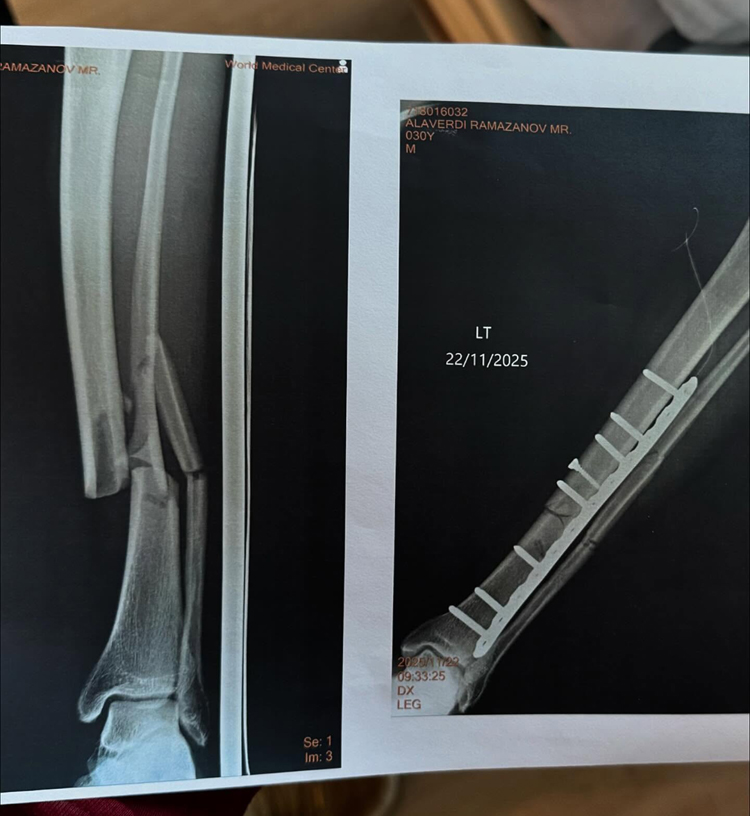

ล่าสุด อลาเวอร์ดี รามาซานอฟ ได้โพสต์ภาพหลังการเข้ารับการผ่าตัด และฟิล์มเอกซเรย์ พร้อมข้อความ "การผ่าตัดประสบความสำเร็จอย่างราบรื่น ขอขอบคุณ ONE เป็นพิเศษสำหรับการดูแลที่ดี และขอขอบคุณทุกคนที่อยู่กับฉันด้วย"